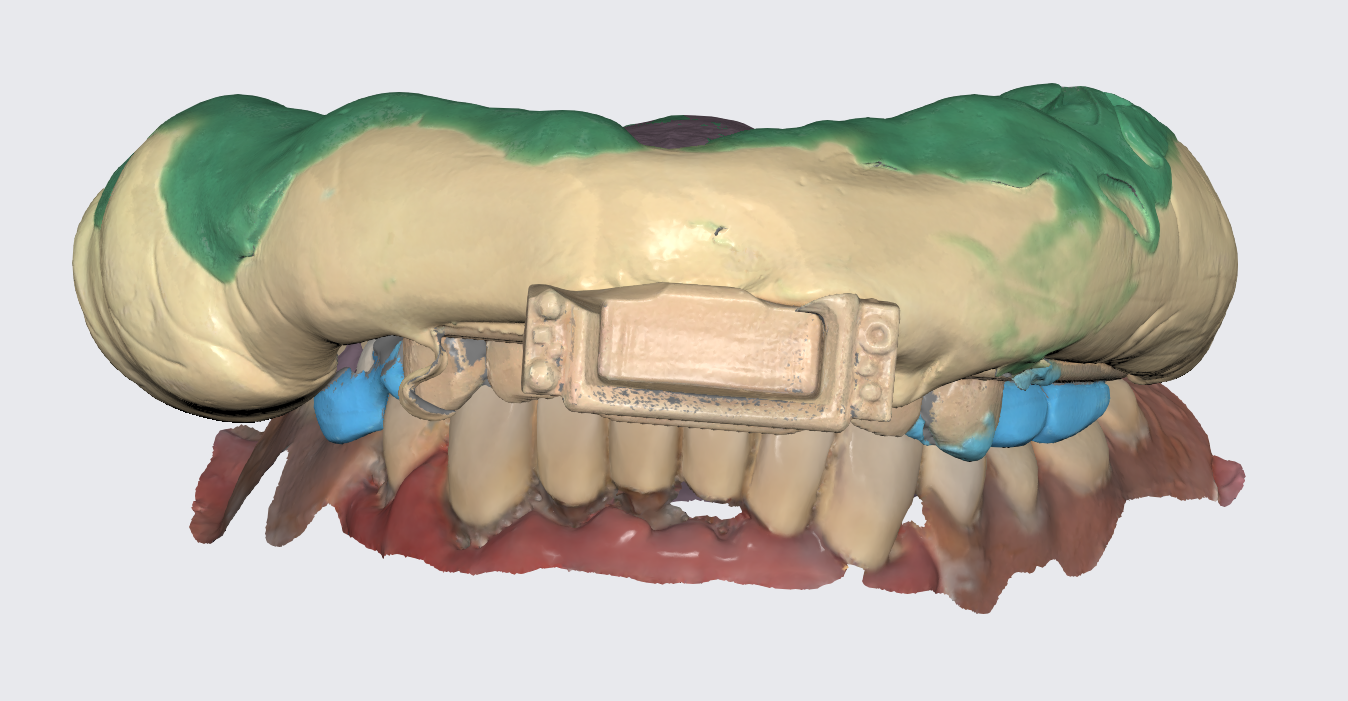

To prepare for the maxillary all on X procedure patient had the upper denture relined with impression material and also multiple dots of radio opaque filling material where temporarily placed on the said denture. Then the 2 dentures where scanned. Also scans of the healed tissues and of the face where recorded.

Shining 3D Metismile face scanner was used to perform the face scan and also alignment of intra oral data with the said face mesh. With the new updates teeth color is corrected on the intra oral scan to match the one recorded by the Metismile so that a more coherent look can be generated. Lip contour was automatically removed from the face scan after data matching.

Another view of the post graft healing in the mandibular arch and visibility of the composite marker additions done on the upper denture for alignment purposes between scan image and CBCT datasets.

A new waxup was generated in Exocad and printed as a try in to check occlusion but also esthetics at some degree and have a proprosthetic implant positioning available in the planning step.